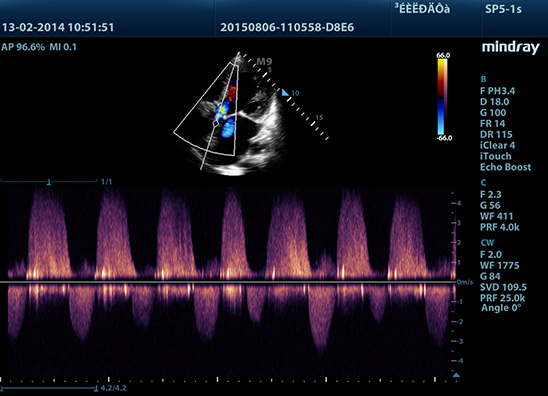

Mindray M9 je dopplerovský ultra ľahký prenosný UZV prístroj najvyššej High End triedy s použitím single crystal 3T sond (vynikajúce zobrazenie blízkeho i vzdialeného poľa), HDR FLOW, ECHO BOOST, Natural Touch Elastography, kontrastného zobrazenia, TDI. Špeciál hlavne pre kardiológiu.

Klinické obrázky: